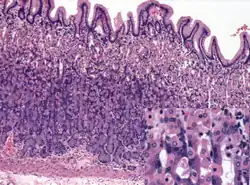

Histology of normal fundic mucosa. Fundic glands are simple, branched tubular glands that extend from the bottom of the gastric pits to the muscularis mucosae; the more distinctive cells are parietal cells. H&E stain.

Histology of normal antral mucosa. Antral mucosa is formed by branched coiled tubular glands lined by secretory cells similar in appearance to the surface mucous cells. H&E stain.